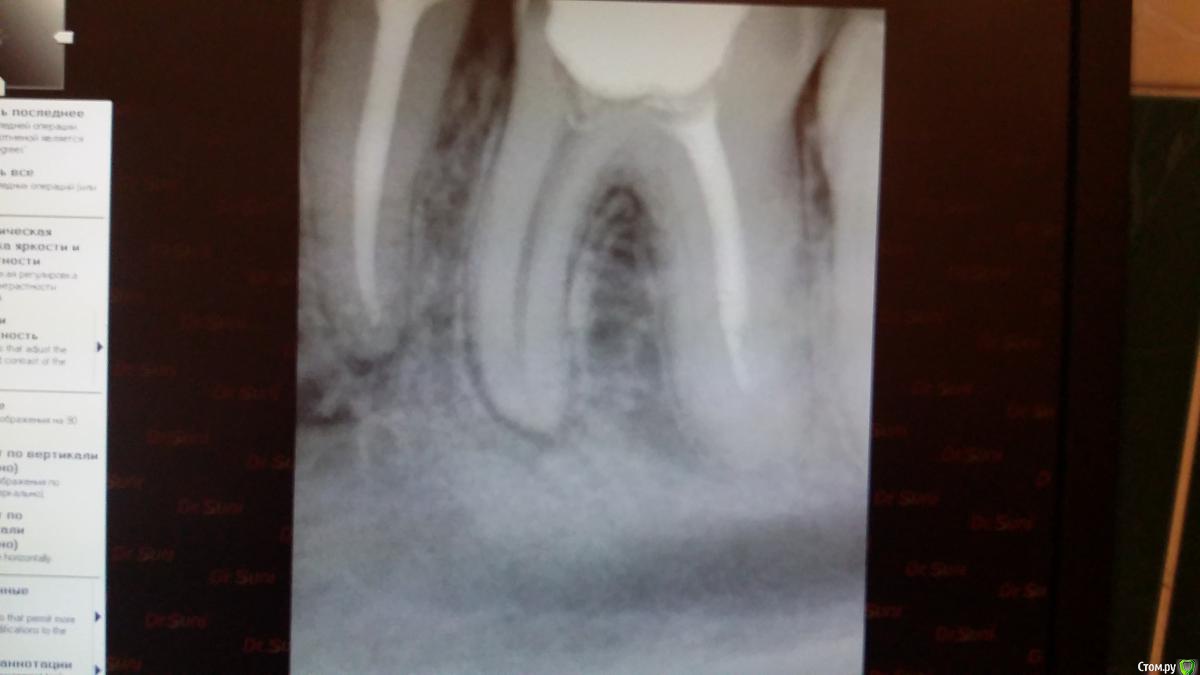

Recive Опубликовано 9 февраля, 2015 Поделиться Опубликовано 9 февраля, 2015 Жалобы: классический пульпит./периодонтитанамнез:эндэндодонтия первичнаялечение:ммо кк первое посещение пульперил, да не будет больеть! Аминь)Второе- в мщ, мя каласепт в дистальном метапаста (ннагнитал каналонаполнителем в надежде найти дельту в апексе)Третье - через неделю замена каласепта на каласепт, и в дистальный крезофен, для надежности.Четвертое на 16.02 пломбировать если не будеет болеть. Ваше мнение и варианты .первый снимок при поступлениивторой при прохождениивторой контроль метапасты и каласепта1.02. 09.02. 1 1 Ссылка на комментарий

Чертков Александр Опубликовано 11 февраля, 2015 Поделиться Опубликовано 11 февраля, 2015 Оценивая динамику рентгенограмм посмею предположить что Вы там создали пробку из опилок - поскольку на рентгенограмме с инструментом Вы у апекса, а на следующей уже "недолёт"...отмывайте нормально канал (нет УЗ- активируйте инструментом) и пакуйте. Коронка - обязательно! 1 Ссылка на комментарий